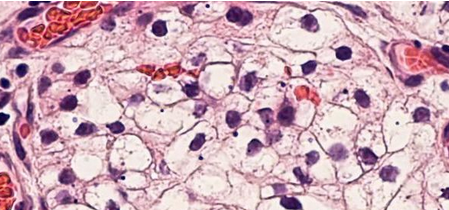

间充质干细胞 (mesenchymalstem cells,MSCs)最早于1976年在Friedenstein等的报道中被提到,当时被称作成骨前体细胞,因其具备分化为各种间充质系细胞的潜能,所以后来被Caplan定义为MSCs。MSCs在体内由于所定居的组织、微环境中的细胞因子和生长因子等各种调控物质的不同,可向不同的谱系分化,不仅可分化为成骨细胞、脂肪细胞、软骨细胞和肌细胞等,还可以跨胚层分化。此外,MSCs具有很强大的自我更新能力,在分化过程中同样可以保持分裂能力。MSCs还具有多种免疫调节功能,它们在体外能够抑制免疫细胞的活化和增殖。MSCs具有这种免疫抑制作用的原因在于其不依赖于主要组织相容性复合物,而是通过细胞膜间的联系和释放可溶性因子来实现对免疫细胞的影响。

研究表明,体内注入了体外扩增的MSCs后能对急性肾损伤产生保护作用并能加速肾功能的恢复。此外,外源性MSCs亦能有效治疗慢性肾病。MSCs有一个特性,它们能够优先归巢到组织损伤区域或者炎症位点。研究显示,静脉内注射的MSCs能够迁移到急性和慢性肾损伤模型动物的肾小球、肾间质、小管周围血管和肾小管。目前,外源性MSCs归巢到损伤动物炎症位点的分子机制还不是完全清楚。不过,趋化因子在炎症部位募集的增多很有可能是引导MSCs迁移的重要原因,此外,外源性MSCs的这种定向迁移和归巢方式与炎症部位趋化因子受体表达特征有关。近来有研究证实,基质衍生因子-1、血小板衍生生长因子和CD44很有可能是调节MSCs归巢的候选对象,这是因为它们相应的受体会在肾损伤后表达上调。但归巢对于MSCs的治疗作用不是绝对必需的,表明MSCs分泌的多种因子的全身性募集才是充分诱导保护效应的主要原因。这些机制虽然在肾脏方面已经有了不同程度的研究,但其详细机制仍不清楚。干细胞进入人体后,干细胞会通过“迁徙”和“归巢”的诱导作用下到达受损的肾脏,这些回输的干细胞一方面能够根据周围微环境分化成新生的肾脏功能细胞;另一方面还能够“催醒”自身肾脏细胞“再生”,通过这种双靶向作用,使肾脏细胞得到最大程度的修复和再生,最后患者肝脏功能逐渐得到恢复。所以通过干细胞技术治疗可以阻止肾细胞的继续病变,阻断肾脏的纤维化进程,使血肌酐下降、预防肾性贫血、肾性高血压、肾性水肿等并发症的发生,也可使尿中蛋白、大便潜血等指标下降甚至转阴,使原发病得到调节和控制。即使肾衰竭的晚期,已经到了尿毒症的严重程度,此时再实施干细胞治疗,也为时不晚。大量的国内外研究结果表明:活性肽具有极强的活性和多样性,在生物体内已发现几百种,不同的活性肽具有不同的结构和生理功能,涉及人体的激素、神经、细胞生长和生殖各领域。

干细胞输入体内后,通过干细胞的归巢作用,加上针对性肾脏有机肽的引导作用,干细胞会转移到肾脏病灶,分化生成所需的各类细胞,从而达到修复肾脏固有细胞,恢复肾功能,重建肾脏血液循环,阻断和逆转肾脏纤维化进程。近年来基础研究干细胞治疗肾病过程中发现,干细胞可分化成肾固有细胞,肾实质细胞等,所以干细胞治疗后对肾脏功能具有良好的修复和重建作用。对于病变较重、病情常反复的患者,干细胞无疑是一种新的有效治疗手段,不仅能控制病情活动,还有可能治愈,对患者的病情带来极大的缓解改善。因为干细胞治疗可以修复受损肾细胞,避免肾功能的完全丧失。与此同时,需要配合其它有效治疗手段来对付病变的肾细胞,辅助性选择透析,适当延长透析时间间隔,甚至可以达到摆脱透析的治疗效果,改善并发症,延缓肾脏衰竭进程,提高生存质量。干细胞主要是采用静脉输注法,患者受到的痛苦少,而且病情已经缓解的不需要住院。患者预后较好,肾脏损伤也较少。在治疗稳定后可以摆脱服用药物。恢复我们身体最大的健康。